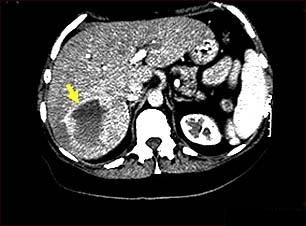

Hemangiomul hepatic